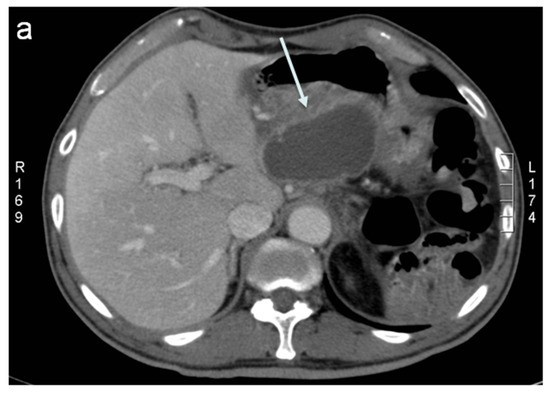

2. Percutaneous Fluid Collection Drainage